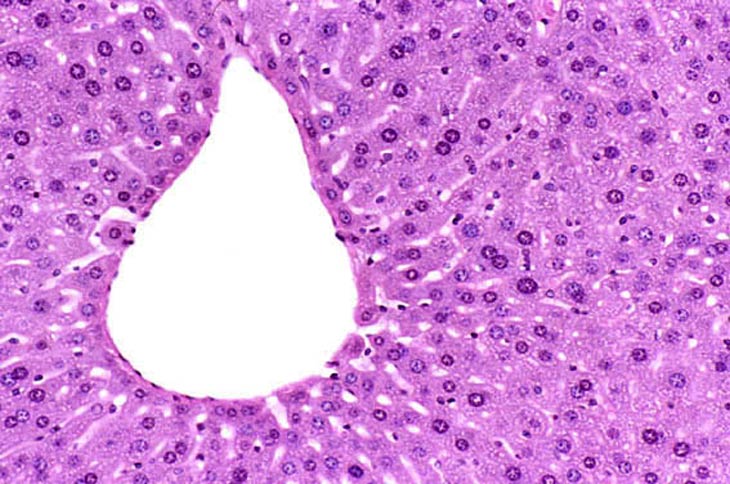

The normal mouse liver contains hepatocytes that are diploid, tetraploid, and octaploid with increase ploidy occurring as the animal ages. A tetraploid hepatocyte may have twice the complement of DNA either by having two diploid nuclei (binucleated hepatocyte) or a single nucleus which contains twice the diploid amount of DNA. A variety of treatment regimens cause alterations in ploidy with single hepatocytes sometimes having several diploid nuclei (multinucleated hepatocytes). The hepatocyte regeneration that follows partial hepatectomy is the result of proliferation of diploid cells. Polyploidy develops once the liver has completed regeneration.

Normal mouse liver showing a mixture of diploid, binucleate, and tetraploid hepatocytes.